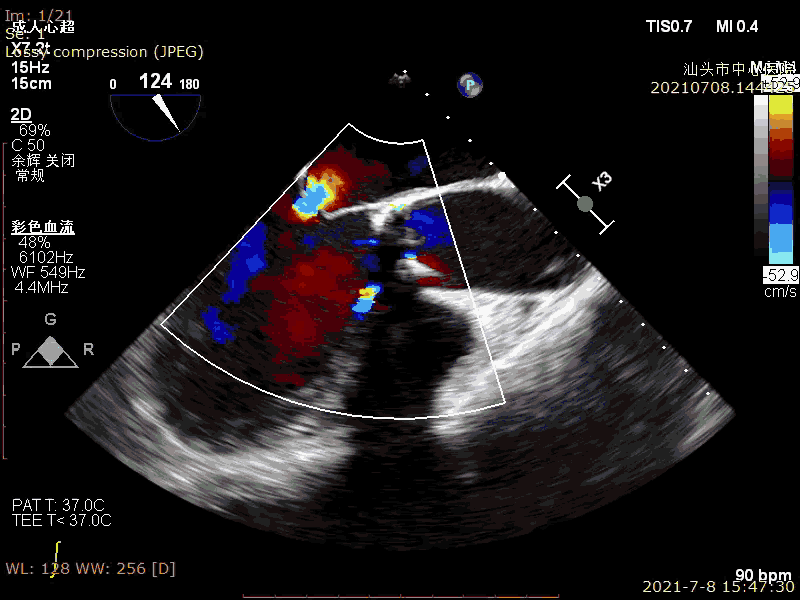

术前超声

术后超声

轻微反流,压差降低

有一定瓣周漏,位置良好

反流明显减轻